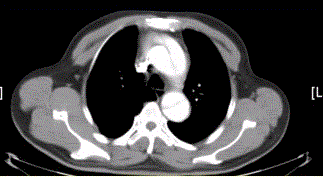

问题 患者男,67岁,高血压病史多年,自服降压药,突发胸骨后剧烈疼痛2h,服用硝酸甘油不缓解。胸透示主动脉增宽。CT影像如下图。 该病例的诊断为

选项 A.主动脉夹层 B.主动脉瘤 C.主动脉破裂 D.主动脉假性动脉瘤 E.主动脉血栓再通 F.大动脉炎

答案 A

解析 A